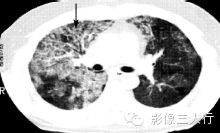

| 病毒性肺炎(图1) | 粟粒性肺结核(图2) | 细支气管肺泡癌(图3) | 肺尘埃沉着病(图4) | 肺泡蛋白沉着症(图5) | 血吸虫病(图6) | |

散在分布,6〜8mm或更小 | 分布均匀,直径1〜2mm | 分布不均,直径6〜7 mm | 分布不均,直径多为2〜5mm | 地图样、铺路石征 | 大小不等,直径多为1〜5mm |

较模糊 | 较清楚或较模糊 | 较清楚 | 较清楚 | 较清楚 | 较模糊 |

病灶密度相同,大小不等 | 病灶密度相同或不同 | 病灶密度相同,呈含气支气管征及蜂窝征 | 病灶密度不均,有钙化 | 磨玻璃密度,地图样分布和铺路石征 | 病灶密度不均,典型者可见晕征 |

(A)平扫一